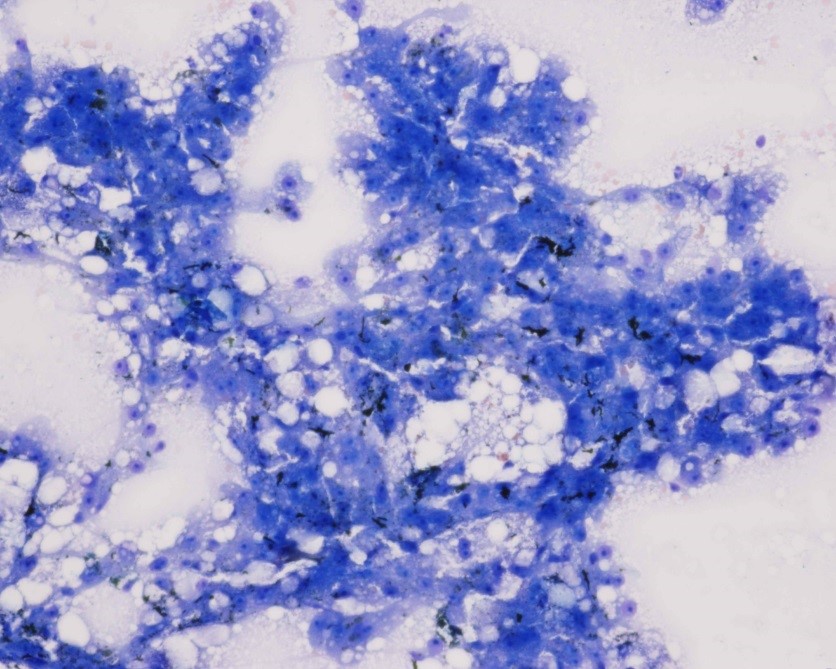

Cytology of fine-needle liver biopsy: Highly cellular sample contains hepatocytes with marked vacuolation and extracellular bile casts.

Low Power view